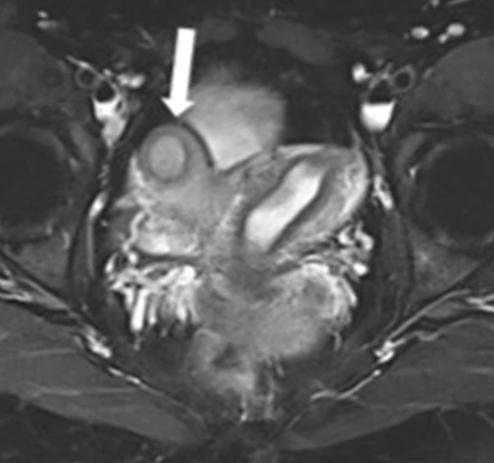

Ces guidelines ont été réalisées sur la base d'un questionnaire envoyé à tous les membres du groupe de travail sur l'imagerie pelvienne féminine (FPI-WG) de la Société européenne de radiologie urogénitale (ESUR), ainsi que d'une revue critique de la littérature agrémentée d’un consensus d'experts La plupart de ces anomalies affectent l'utérus. Cependant, le spectre des FGTCA est large, englobant des anomalies du col de l'utérus, du vagin, de la vulve et des trompes de Fallope, avec ou sans malformations associées de l'ovaire, des voies urinaires, du squelette ou d'autres organes.

Tous les protocoles incluent des séquences d’IRM en T1 avec ou sans Fat Sat, toujours en axial avec ajout de plan sagittal quelquefois. De même, des séquences T2 multiplanaires du bassin en orientation strictement axiale, sagittale et / ou coronale sont toujours réalisées, ainsi que des séquences orientées par rapport à l’utérus. Ces dernières sont plus couramment obtenues par une combinaison de vrais coronaux et vrais axiaux du fond et du corps de l'utérus. La séquence 3D-T2 du bassin, permettant le reformatage multiplanaire (MPR) de l'utérus, est quelquefois utilisée bien que cette séquence fasse l’objet d’une qualité de d'image faible.

Les auteurs de cette étude remarquent que les capacités multiplanaires et la bonne résolution pour les tissus mous de l'IRM fournissent une excellente évaluation du large spectre de manifestations radiologiques des FGTCA. Un protocole d'imagerie normalisé et une un compte rendu uniformisé garantissent, dans ce cadre, une mise en lumière de ces résultats, contribuant à un diagnostic et à une classification corrects des FGTCA, des pathologies associées et de leurs complications.